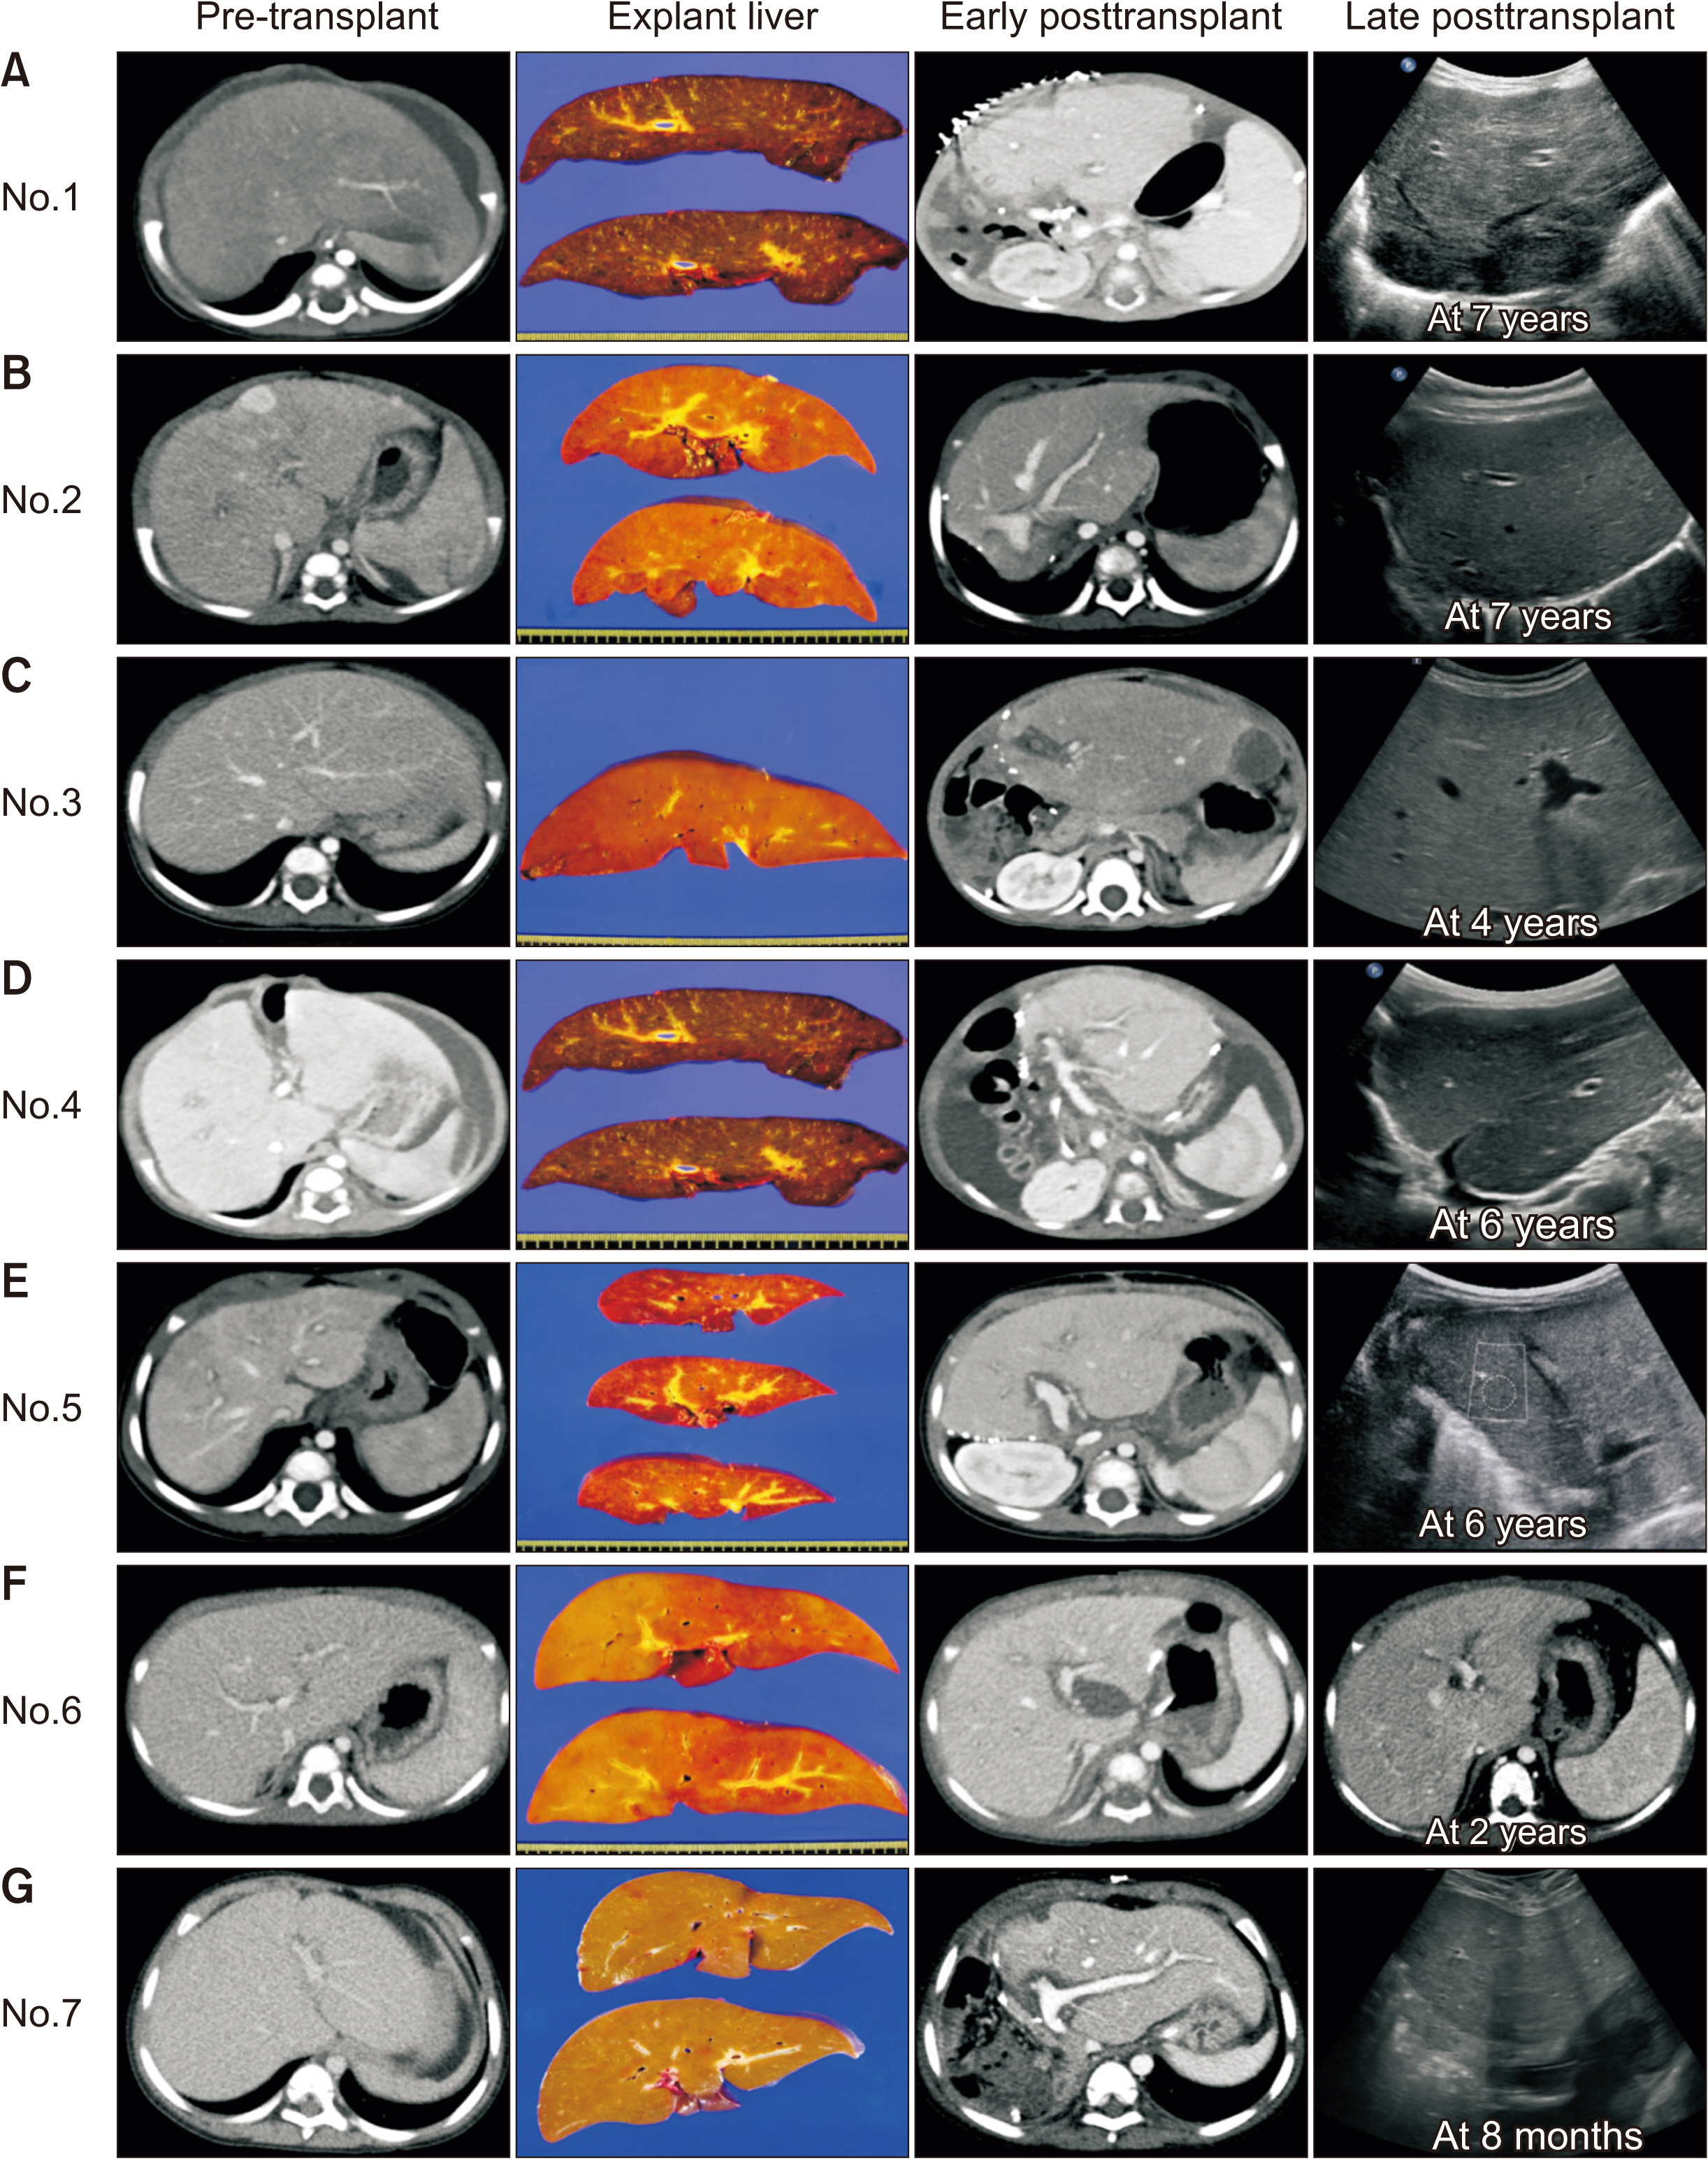

Two and five patients were diagnosed with PFIC type 1 and type 2, respectively. For all seven patients, age of PFIC onset was at birth. Jaundice was present in all cases. Mean pretransplant total and direct bilirubin levels were 16.1 ± 8.1 mg/dL and 12.4 ± 6.2 mg/dL, respectively. Median patient age and body weight at LT were 10 months and 7 kg, respectively. Types of donors were mothers of patients in four and deceased donors in three. All five patients with PFIC type 2 recovered uneventfully. One patient each with PFIC type 1 underwent retransplantation due to graft failure or died due to multi-organ failure. Overall graft and patient survival rates at five years were 66.7% and 83.3%, respectively. Bile salt export pump immunohistochemical staining showed normal canalicular expression in two patients with PFIC type 1, focal loss in two patients with PFIC type 2, and total loss in three patients with PFIC type 2.

LT is currently the only effective treatment for PFIC-associated end-stage liver diseases. It is mandatory to perform regular follow-up due to the risk of complications including steatohepatitis, especially for patients with PFIC type 1.